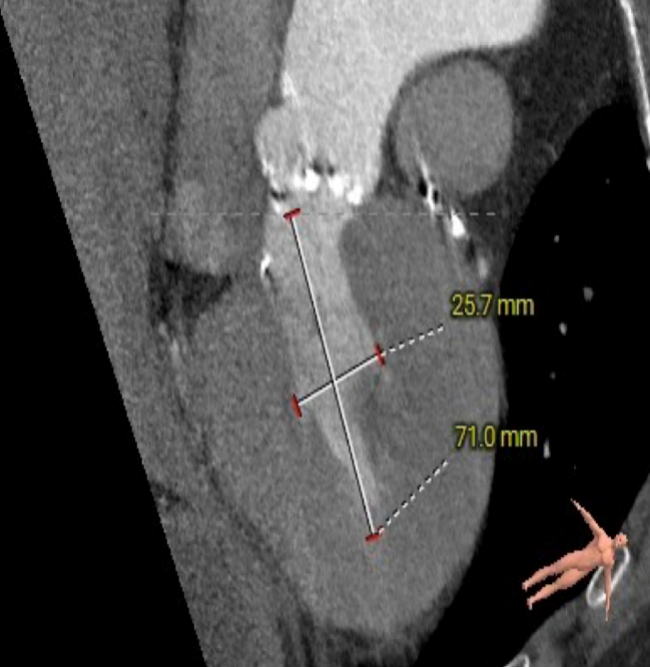

主动脉瓣瓣环周长97.1mm,平均周长径 30.9mm,SOV:34.8mm*47.5.3mm*42.4mm,瓣叶增厚,瓣上钙化分布不均,瓣环水平夹角66°。

冠脉高度测量

LEFT CORONARY

左冠开口高度20.4mm

RIGHT CORONARY

右冠开口高18.8mm

钙化分布:HU850钙化积分881mm³